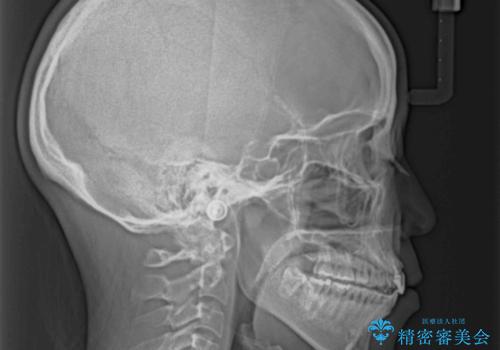

抜歯矯正の後戻り インビザラインによるオープンバイトの再矯正

- 以前矯正治療をされていましたが、後戻りが起きたことを気にして来院された患者様です。

上下前歯のオープンバイトを改善するため、インビザラインにて治療を行うこととしました。